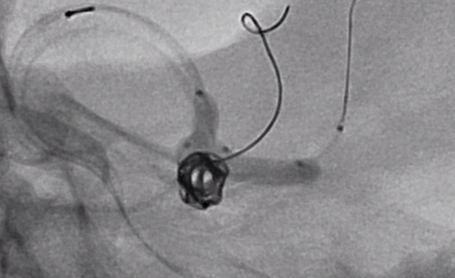

En este aneurisma se realizó la cateterización con dos balones de remodeling Eclipse 2L con microguías Traxcess y Ashahi .014, realizando dos cambios de curva para el cateterismo distal. El acceso proximal se realizó con un introductor largo Ballast .088 de 90cm que permite el uso de dos balones y un microcatéter para introducir los coils.

Con un buen posicionamiento de los balones se logró el cierre completo del aneurisma con seguridad y control garantizando la permeabilidad de las ramas. En este caso no se completó el tratamiento con stent por que la paciente debe someterse a una cirugía reciente.